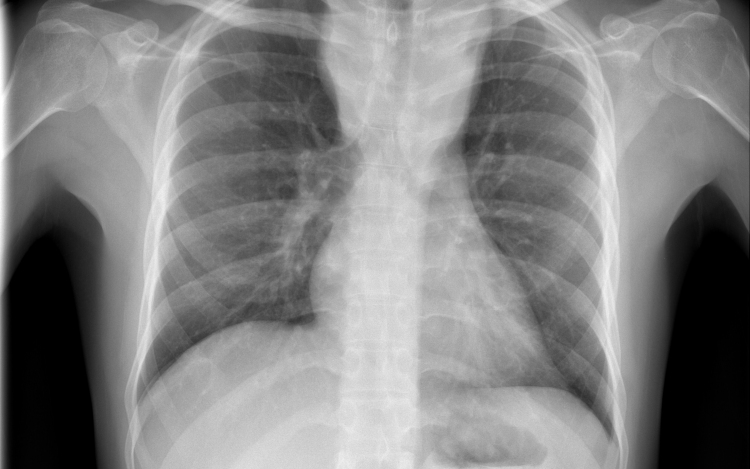

Csökkent a tbc-fertőzések száma Európában

Átlagosan 4,3 százalékkal csökkent az új tuberkulózisos (tbc-s) esetek száma 2010 és 2014 között az Egészségügyi Világszervezet (WHO) 53 országot magába foglaló európai régiójában.

A becslések szerint 2014-ben 340 ezer európai betegedett meg tuberkulózisban, ami százezer emberre vetítve 37 esetnek felel meg. Azzal, hogy 2010 és 2014 között átlagosan 4,3 százalékkal csökkent az új esetek száma, az európai régió teljesítette azt a millenniumi fejlesztési célt, hogy 2015-re visszafordítja a tbc terjedésének tendenciáját.

Magyarországon biztonságos a tbc-re vonatkozó epidemiológiai helyzet: 2014-ben nyolc új eset jutott százezer lakosra, és az előzetes adatok szerint ugyanez igaz a 2015-ös évre is. Így a WHO Magyarországot az alacsonyan átfertőzött országok között tartja nyilván. Alacsony a multirezisztens esetek száma - 2014-ben hét új esetet észleltek -, valamint a gyermekkori megbetegedéseké is: 2014-ben hat 14 éven aluli gyermek betegedett meg.

Az európai régióban ugyanakkor továbbra is nehezíti a tbc felszámolását a multirezisztens tbc és a tbc magas előfordulási aránya a lakosság sérülékeny csoportjaiban (hajléktalanok, kábítószer- és alkoholfüggők, magas fertőzöttségi arányú országokból érkező migránsok) - áll a közleményben. Ezeknek a szegény és marginalizálódott csoportoknak az eléréséhez az ECDC tudományos útmutatást adott ki a közelmúltban.

A WHO a legnagyobb kockázatnak kitett csoportok célzott tbc-szűrését javasolja, Magyarországon 2014 óta eszerint szervezik meg a kötelező tüdőszűrést.